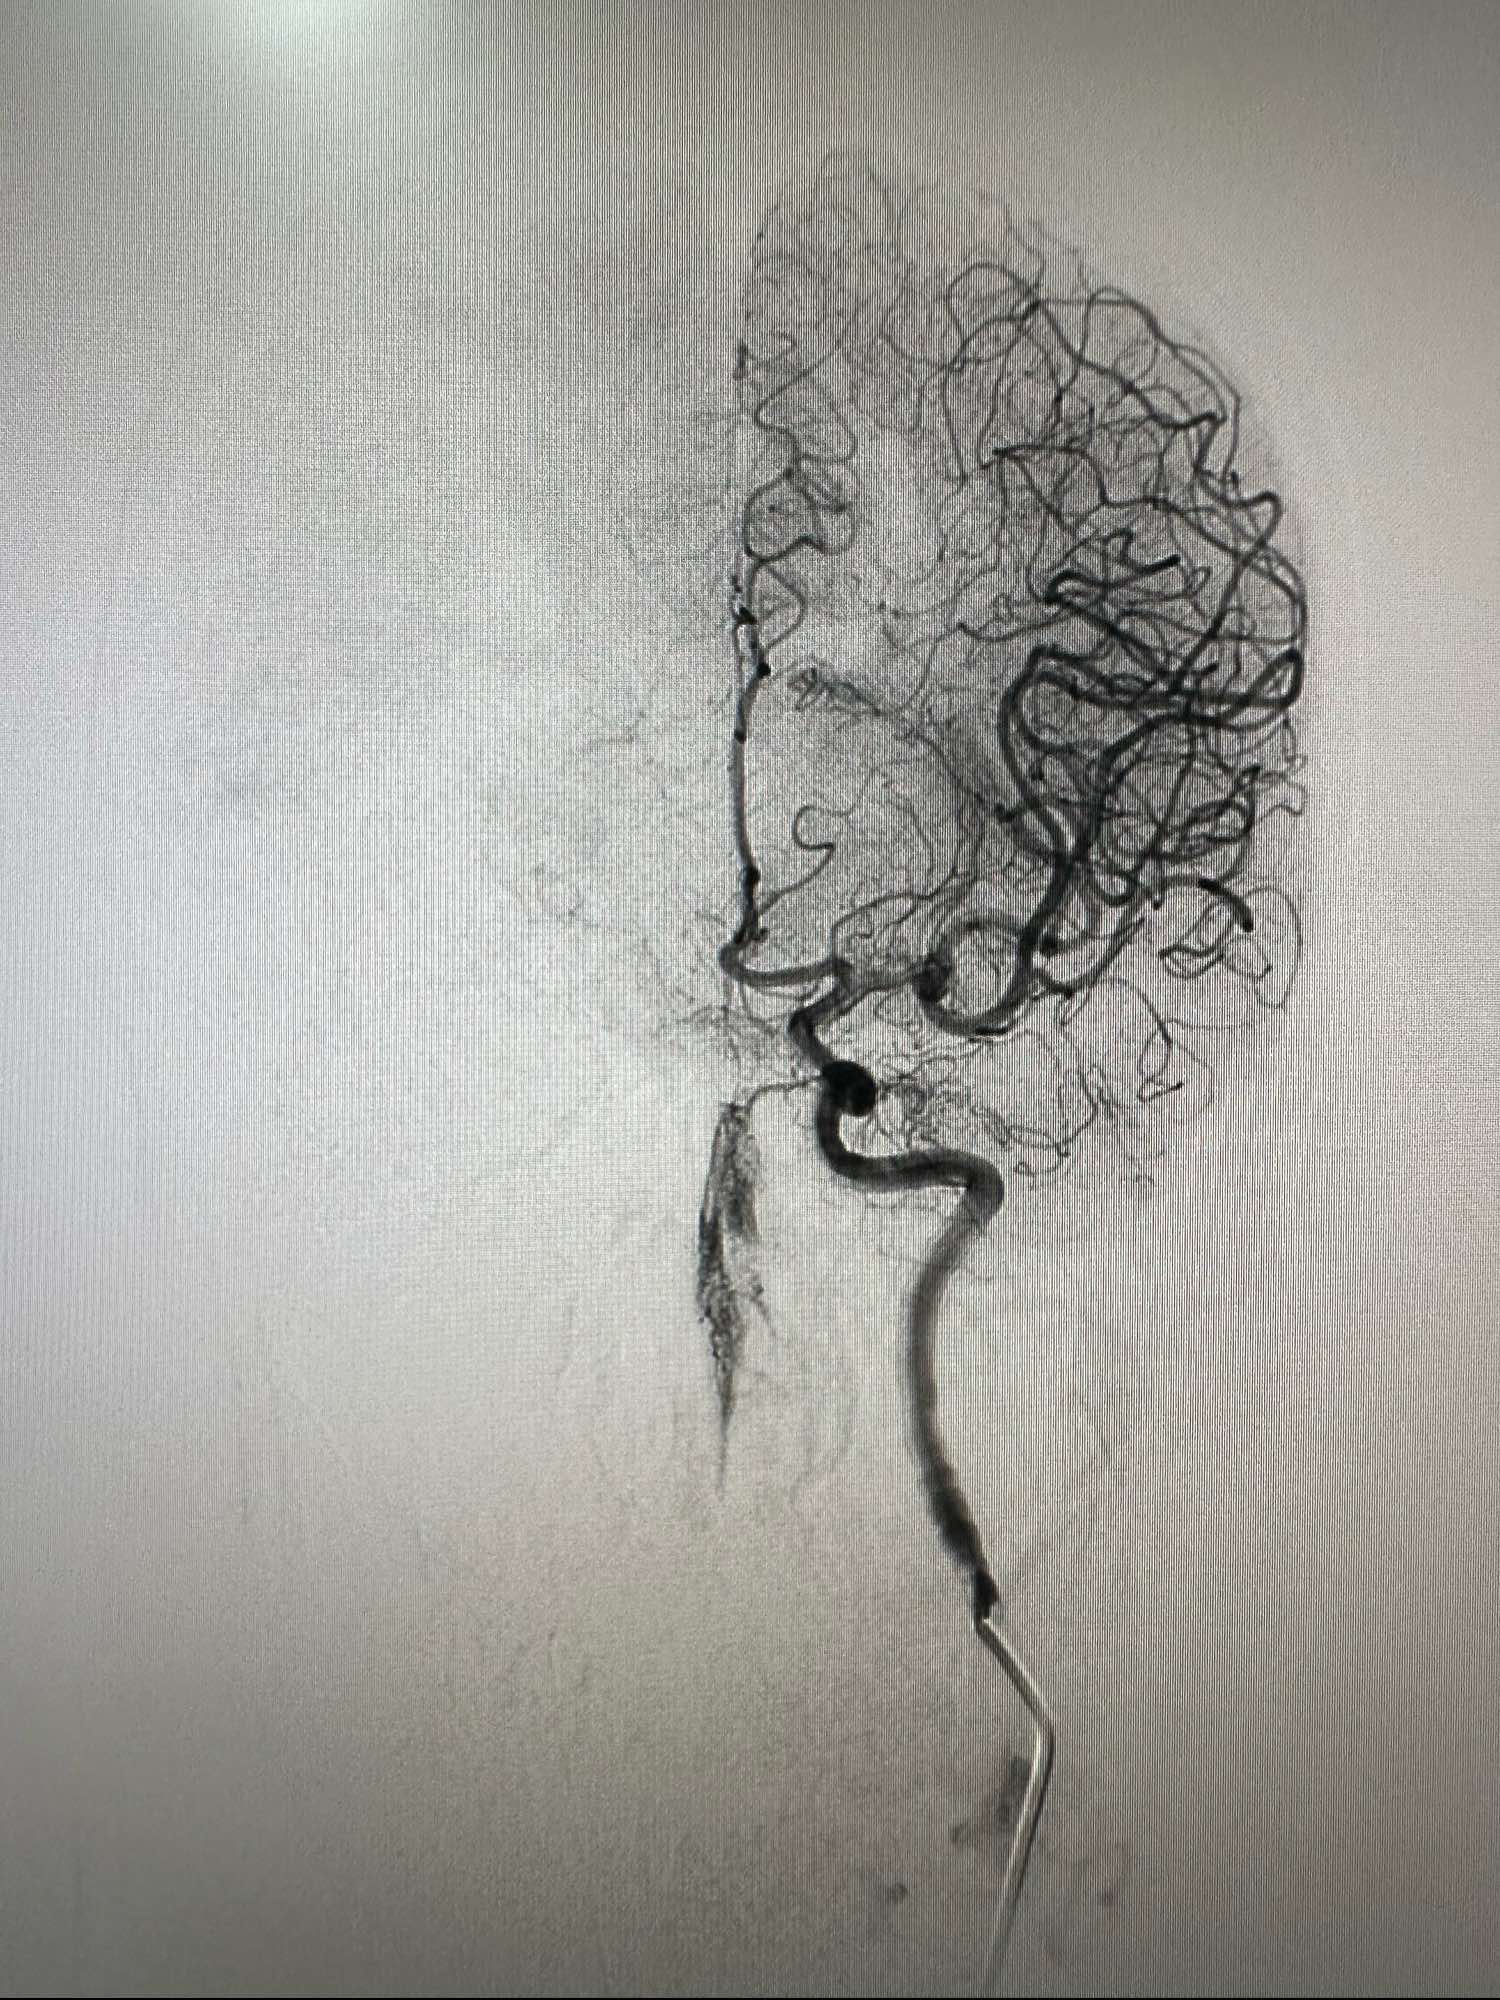

左侧颈内动脉造影正位

侧位